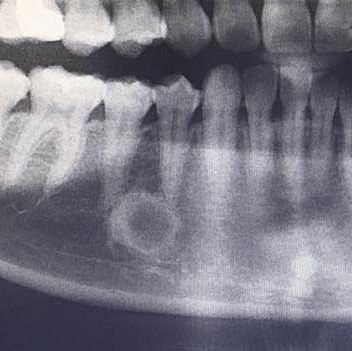

这是牙齿的x光片,那个牙齿根部的圆形是什么东西,要不要紧